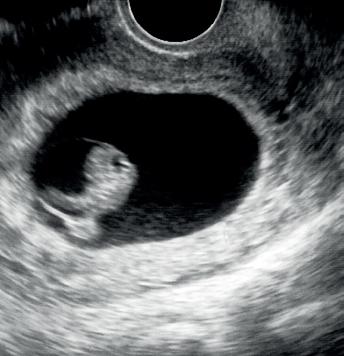

Våre erfaringer med hjemmeinduksjonsstudien er at dette bør være et alternativ til kvinnene som induseres, og vi har tatt metoden inn i vår lokale induksjonsprosedyre. Hos oss har vi gjort enkelte endringer etter studien, blant annet kan kvinner med vannavgang også få misoprostol hjemme. Ellers har vi økt til maks 8 tabletter i 2 påfølgende dager, men kvinnene kommer inn til sykehuset neste dag for å hente resterende 8 tabletter. På denne måten sparer vi tabletter som ikke blir brukt, og ikke minst får vi en kontakt med kvinnene slik at de lettere kan gi beskjed om problemer, spørsmål eller annet. Vi tar kun CTG før 1. dose misoprostol. Kvinnene som egner seg informeres om at de kan være hjemme, istedenfor at de informeres om at det er en mulighet å være hjemme. Alle får skriftlig informasjon om hvordan de skal ta tablettene hjemme og når de skal henvende seg til avdelingen. Flyten og den praktiske gjennomføringen av induksjonsstrømmen er vi således allerede i gang med å optimalisere.

Inntrykket vårt er at det å være hjemme i starten av induksjonen gi mer ro, komfort og trygghet totalt enn det vi kan tilby ved innleggelse, spesielt for flergangsfødende. Vi tror også at tabletter fremfor ballong kan være en enkel, skånsom og praktisk måte å bli indusert på, som både vi og kvinnene det gjelder vil trives med. Vi kommer gjerne tilbake med tall og resultater.

Fortsettelse følger!

25 Medlemsblad for Norsk Gynekologisk Forening

Kikhostevaksine

Gravide blir en målgruppe i barnevaksinasjonsprogrammet